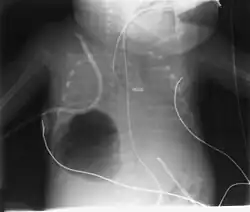

Los neumatoceles son especialmente frecuentes en niños y no deben confundirse con otras acumulaciones de gas en el tórax, como el neumotorax, las bullas que se producen en el enfisema pulmonar o el absceso de pulmón. Se diagnostican mediante una radiografía o TAC de tórax que permiten ver un espacio lleno de aire que contrasta con el parénquima pulmonar que lo rodea. Suelen desaparecer de manera espontánea, aunque en ocasiones es preciso realiza un drenaje mediante la inserción de un cateter para lograr su resolución.[1][2]